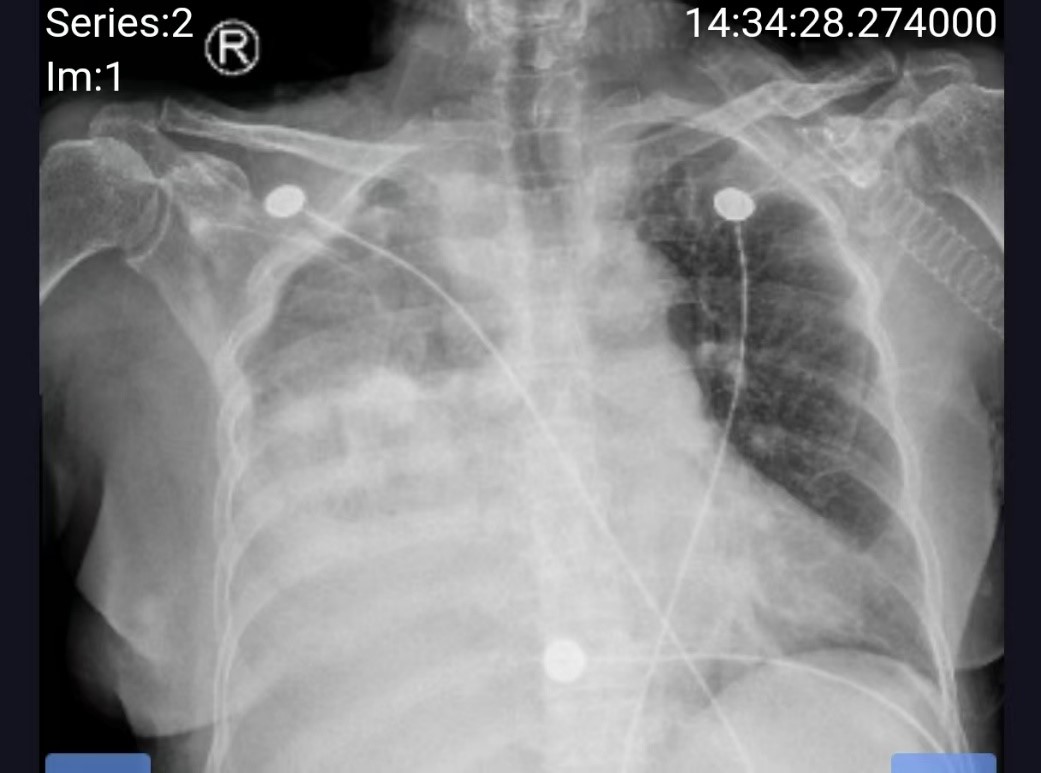

在多学科医护人员的共同努力下,韩阿姨顺利接受了胸腔穿刺引流,引出大量胸水。复查胸片显示肺部的阴影正逐渐消散,针对性调整抗感染方案,病情进一步趋于稳定。